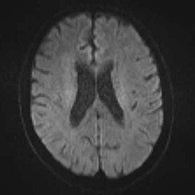

<術後画像所見>

頸部狭窄は解消しており、新たな脳梗塞など生じていない。

<術後画像検査>

術後はバイパス血管が脳内に向かって出現している(赤丸印)。